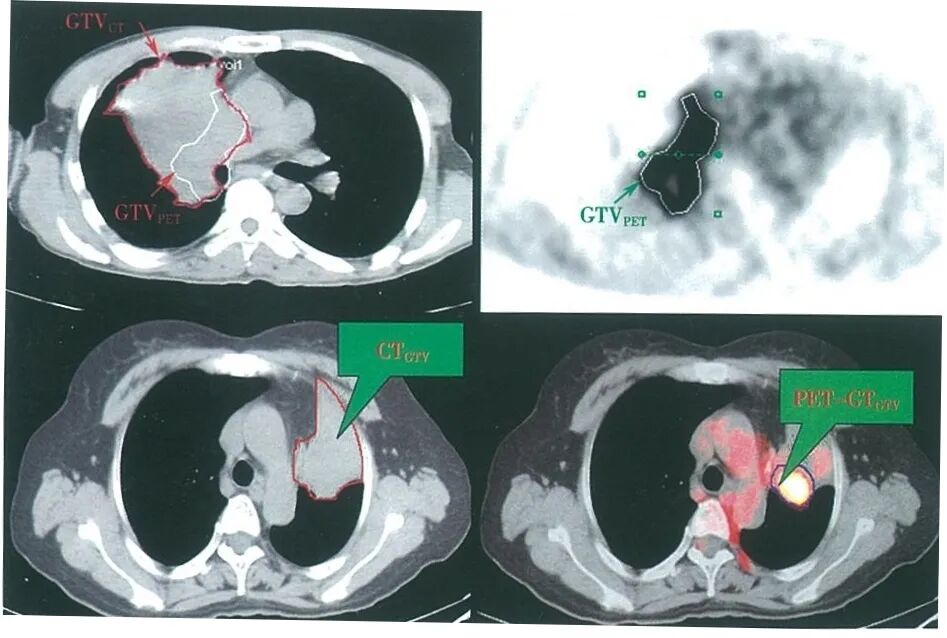

◾ 指导制定放疗计划、勾画放疗靶区

肺癌伴肺不张靶区勾画